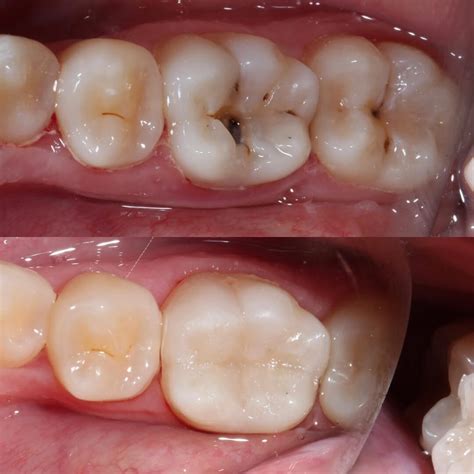

7. Restoration: Finally, the access hole is filled with a temporary or permanent filling. A crown is often recommended afterward to protect the tooth.

Once you have successfully undergone the procedure, it is important to treat the tooth with care. Even though the nerve has been removed, the tooth structure remains. Because the tooth can become brittle over time without the internal blood supply, your dentist may suggest a dental crown to provide structural support and prevent fracturing. Good oral hygiene—including daily brushing and flossing—is essential to prevent secondary decay. Regular dental check-ups are also vital to ensure the tooth remains healthy and the seal stays intact.